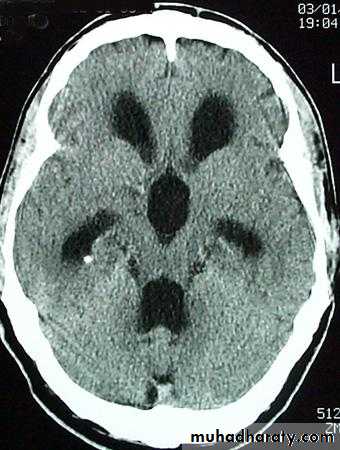

Meningioma

Benign tumor arise from the arachnid cells of the meningeal covering of the brain are most common primary intracranial neoplasm

Usually present in middle age female

it is well defined extra axial , located mainly at the convexity of the skull periphery

CT finding

meningioma presented as isodense area or slightly hyper density area with surrounded crescent of hypo density ( csf cap ) post contrast injection the lesion enhance homogeneously with enhancing Dural tail .

20 % show calcification

hyperostosis & thickening of the near by bony part of the skull & diplioc space .

it may be associated with little or no peri focal edema .

if the lesion associated with central necrosis with large perifocal edema meningio sarcoma should be excluded .